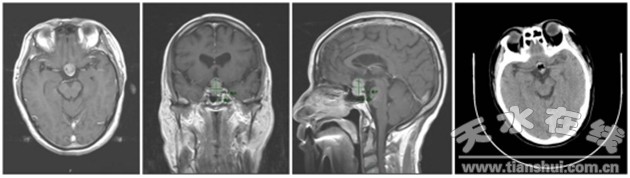

(垂體瘤神經(jīng)內(nèi)鏡下手術(shù)中照片及手術(shù)前后影像片)